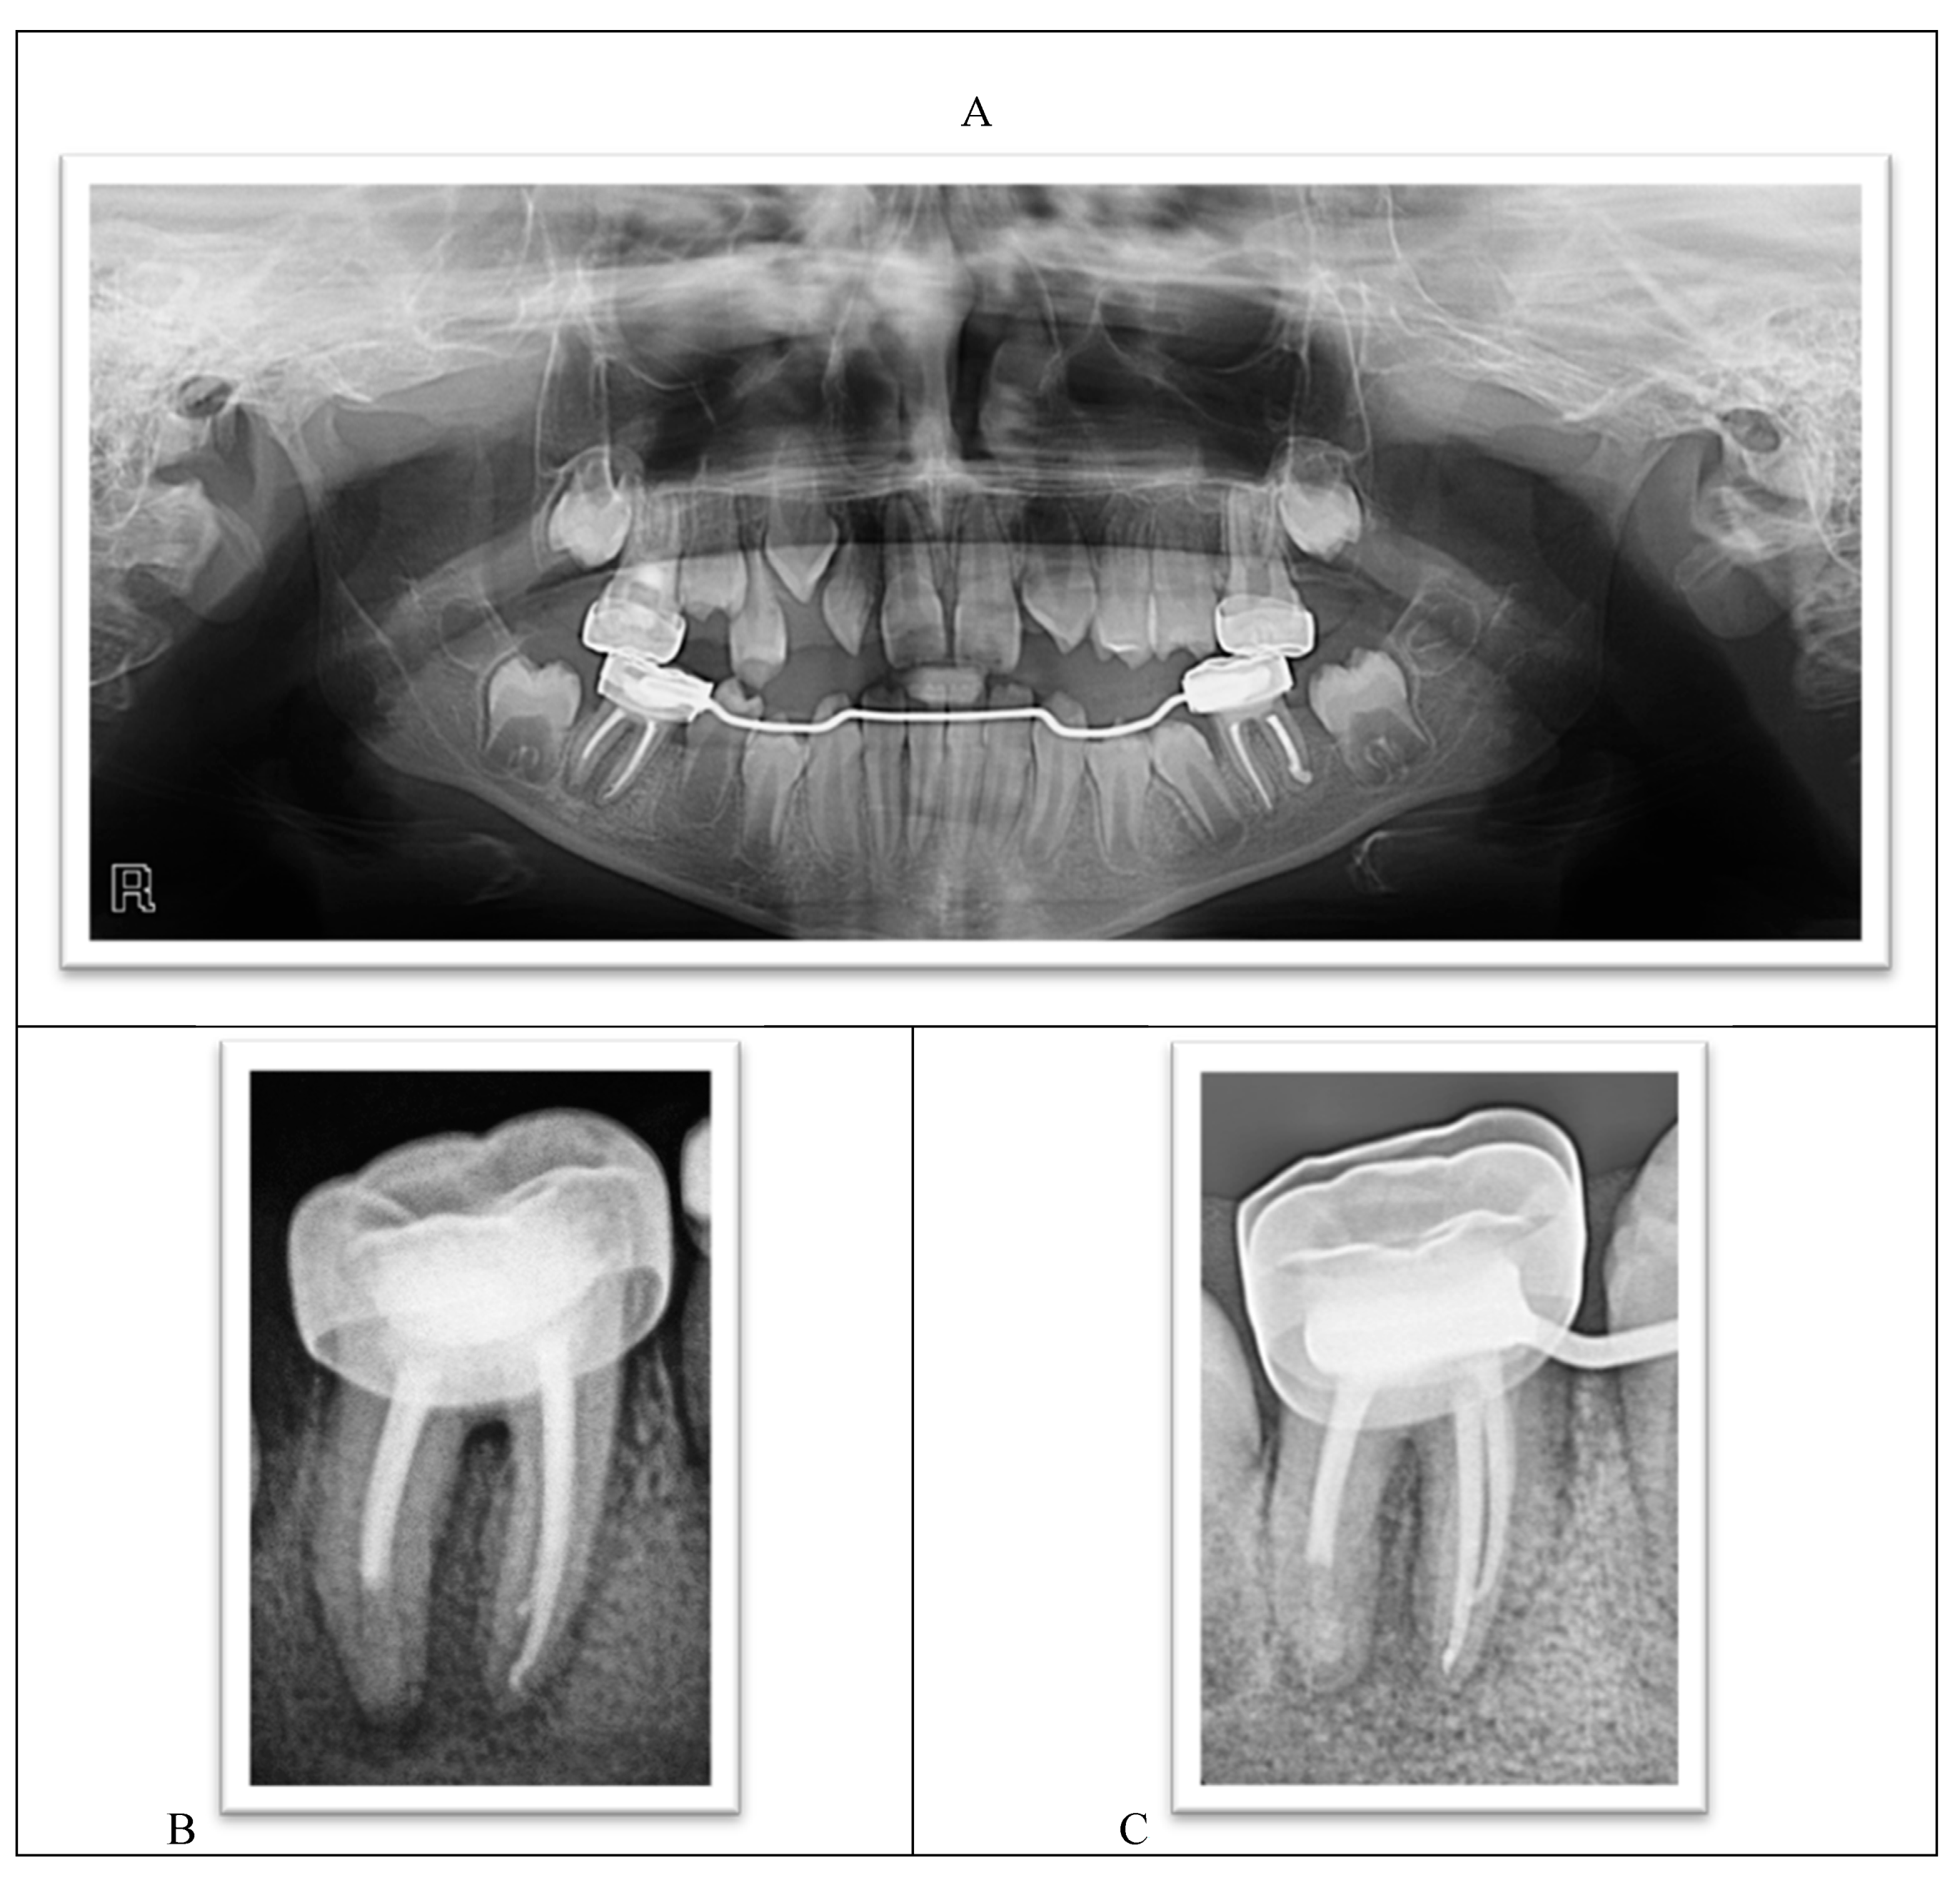

- Working length was established using a radiograph.

- Mesial canals were obturated with gutta-percha using a lateral condensation technique while the distal root was treated with MTA as an apical plug because there was no apical stop.

- A moist cotton pellet was placed in the canal to facilitate MTA setting, and the access cavity was restored using a glass ionomer cement.

- The next day, the setting of the MTA plug was verified, and the remaining portion of the root canal was filled with gutta-percha using lateral condensation. The pulp chamber was cleaned and the coronal access double-sealed with a bonded resin composite.

- A stainless steel crown was inserted.